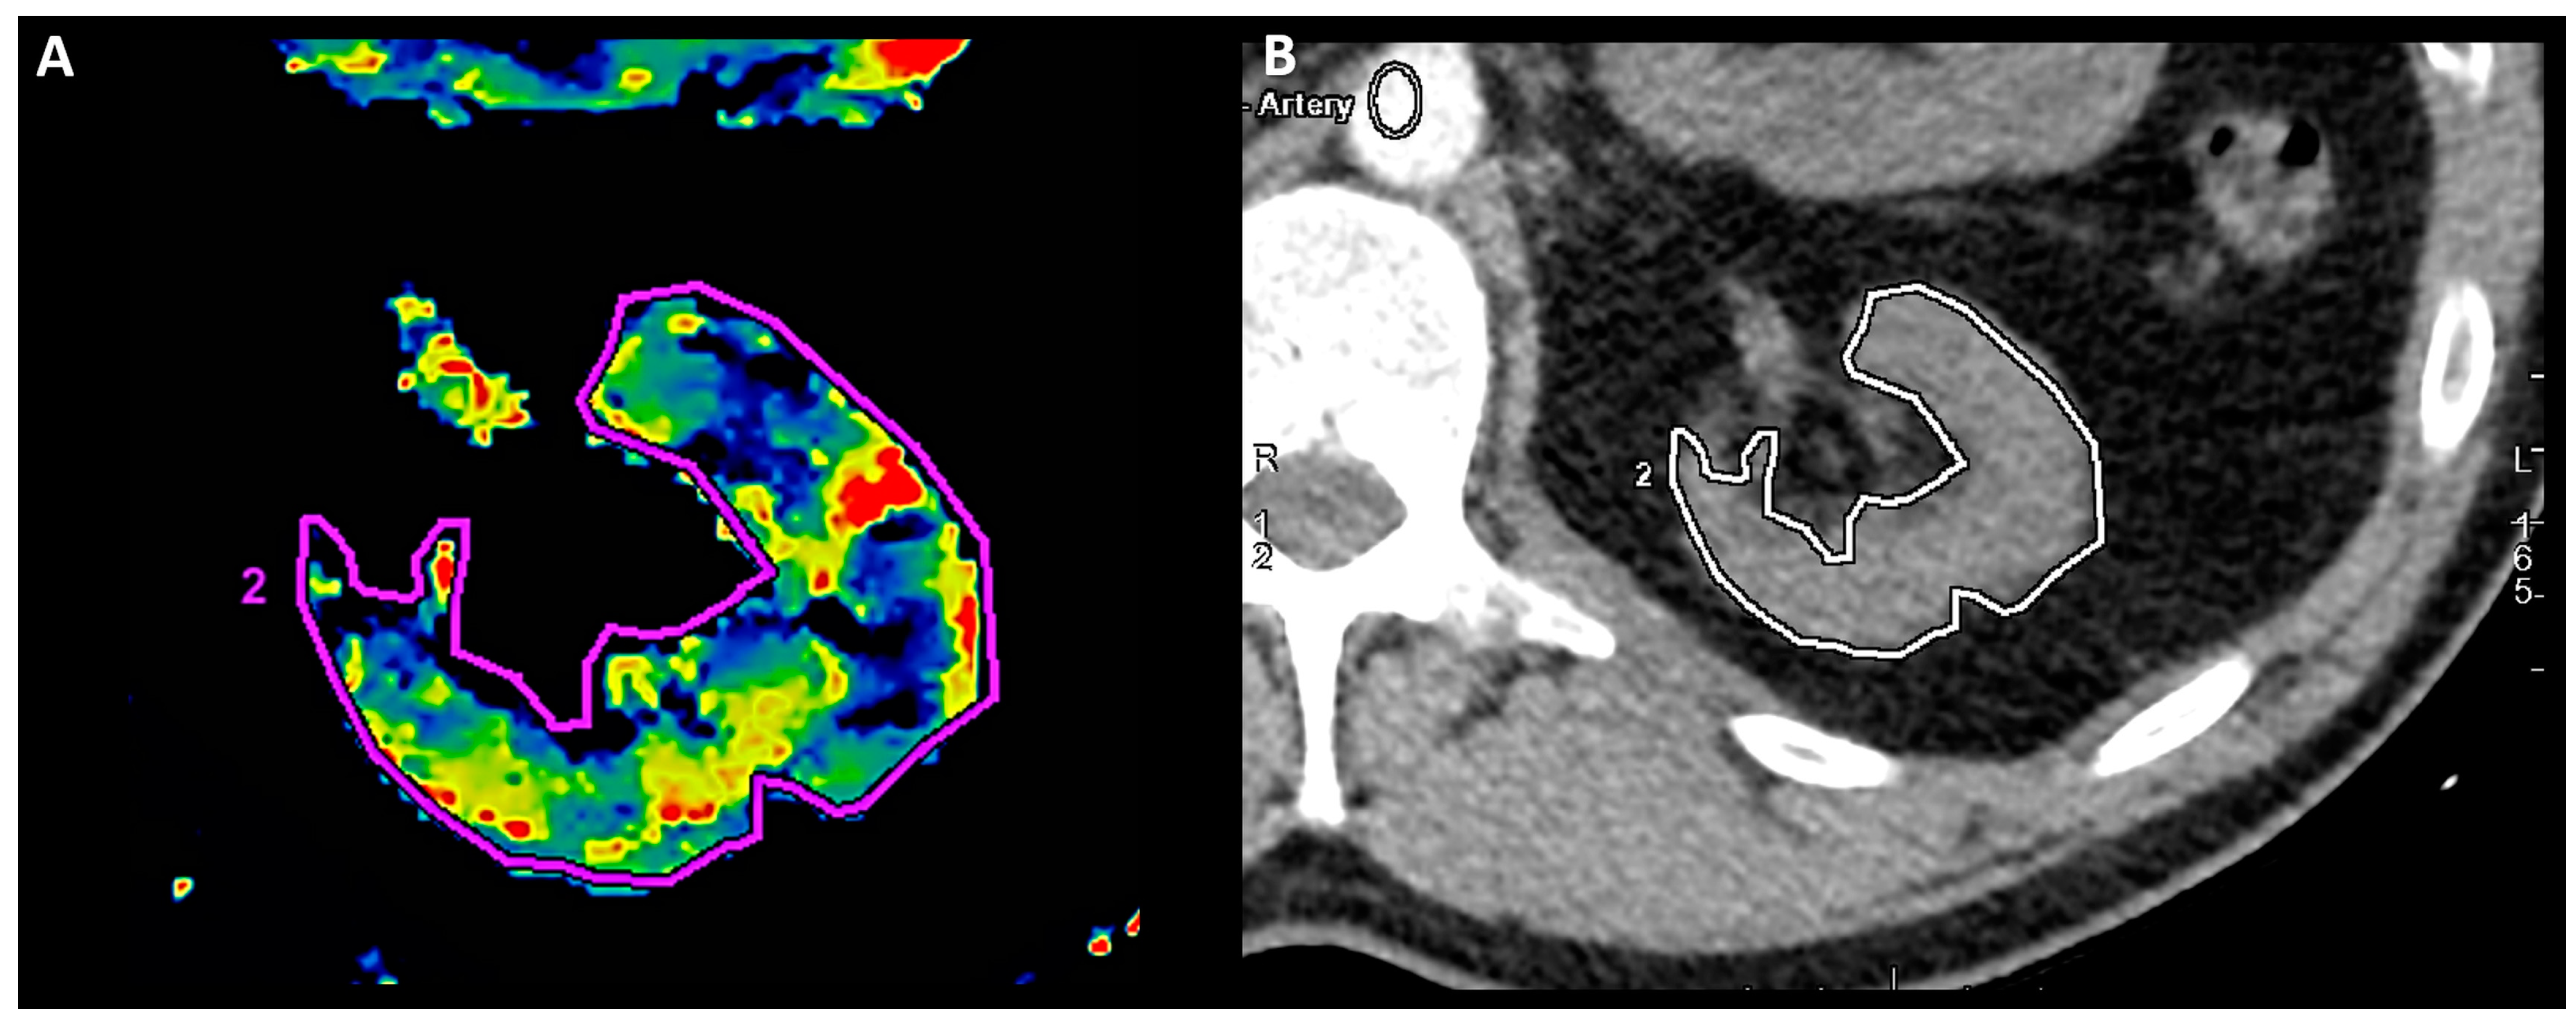

2.2. Contrast-Enhanced Multidetector Computed Tomography

2.2.1. CE-MDCT Protocol

2.2.2. Renal Artery Stenosis Measurement